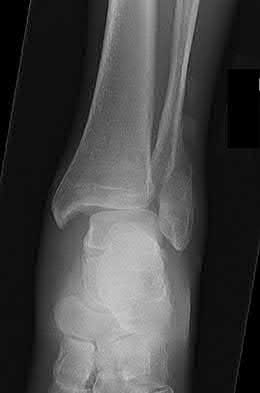

A 28-year-old male sustains a severe hyper-dorsiflexion injury to his ankle in a motor vehicle accident, resulting in a Hawkins Type III talar neck fracture. Which of the following arteries provides the predominant blood supply to the body of the talus, placing it at significant risk for avascular necrosis in this injury?

The artery of the tarsal canal, which is a branch of the posterior tibial artery, provides the dominant blood supply to the talar body. In a Hawkins Type III fracture (talar neck fracture with subtalar and tibiotalar dislocation), the blood supply from the artery of the tarsal canal, the artery of the sinus tarsi, and capsular vessels are disrupted, leading to an avascular necrosis (AVN) rate approaching 100%.